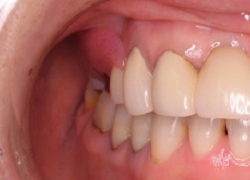

ノンクラスプデンチャーは,

金属のバネが見えないので,見た目が良好です.

(ポリアミド高分子樹脂↓:エステショット使用例)